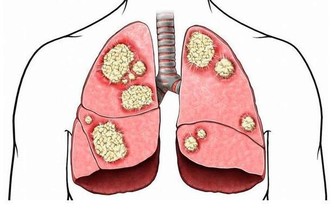

茶有抗氧化的作用,喝茶可以讓血管壁光滑,減少血管堵塞的風險,幫助預防三高,茶中的茶多酚可以幫助人體清除自由基,有良好的抗癌作用,還可以提高人體的免疫力。喝茶還能陶冶人的性情,修身養性。內外兼修,自然能長壽。